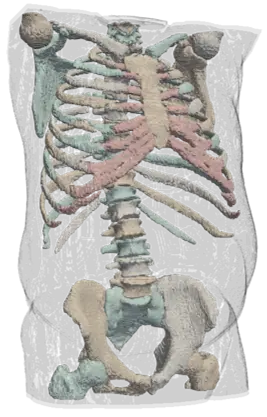

Exemples de segmentation par IA

squelette

Depuis un scanner - Chaque landmak est indépendant.